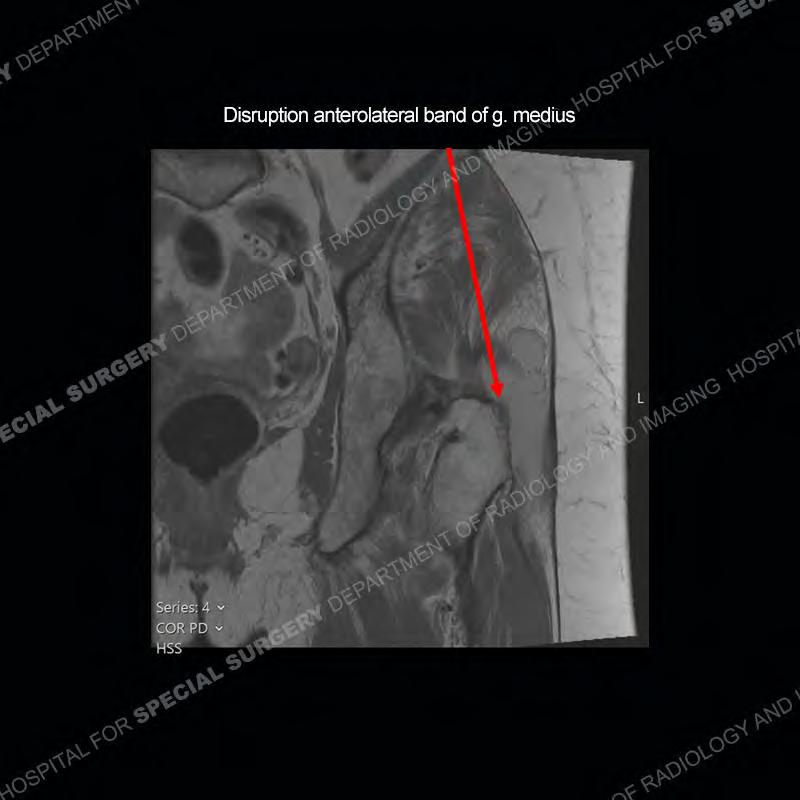

The radiograph is not particularly contributory in this case. The MRI demonstrates markedly abnormal architecture of the gluteus minimus and anterolateral band of the gluteus medius. Portions of the tendons are high signal, portions are highly attenuated, and portions are disrupted. A large, complex fluid collection is present in the adjacent soft tissue.

Diagnosis: Gluteal Tendinosis and Disruption with Complex Trochanteric Bursal Collection

Not as much of a diagnostic dilemma as many of the other cases shown but just a nice example of the pathology seen of the gluteal tendons and a cause of trochanteric pain. Although, frequently thought of in isolation, trochanteric bursitis or bursal thickening is much more commonly a reactive change to underlying pathology of the subjacent gluteal tendons. The gluteus medius is divided into a posterior band and an anterolateral band. Tendinosis and partial tearing very commonly will involve the gluteus minimus and especially the more posterior fibers and then propagate into the anterior lateral band of the gluteus medius. Involvement of the posterior band of the medius is much less common and engenders a marked degree of functional impairment.